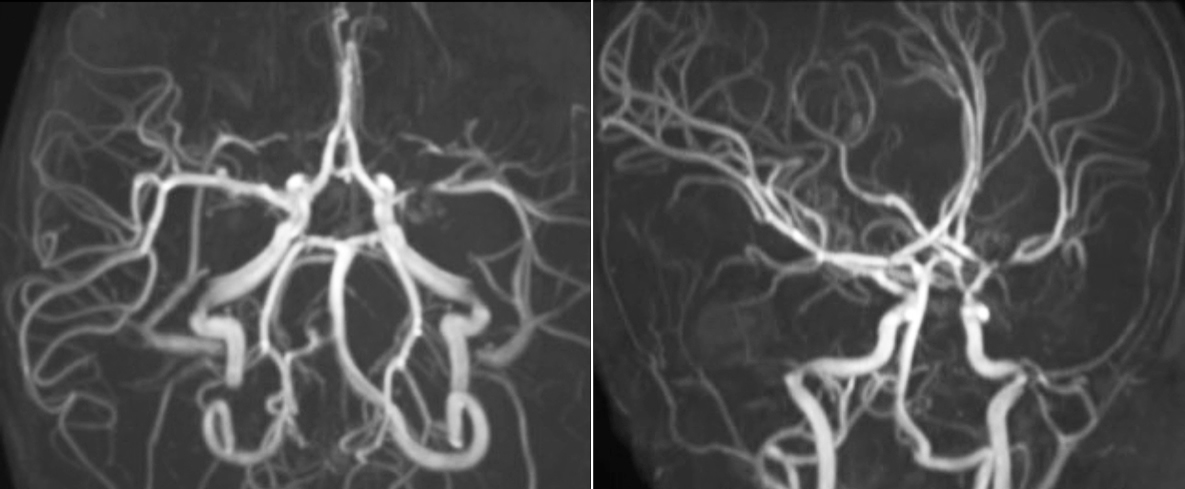

SWIp supports diagnostic confidence in traumatic brain injury

The value of susceptibility weighted imaging in visualizing brain injury is well documented. The Philips multi-echo SWIp technique provides fast susceptibility weighted imaging with enhanced susceptibility contrast and high resolution.

“Pediatric imaging is not without its challenges,” Dr. Miller says. “Since our patients are often very small, we need very high-resolution imaging. In cases of brain injury, we need to obtain information quickly so the treating clinicians can make decisions on care. We rely on high resolution and robust imaging capabilities, and SWIp provides that.”

“SWIp helps us identify blood or blood products, calcification, and diseases that affect the vascular system,” says Dr. Miller. “In children with traumatic brain injuries, it highlights areas that are injured, better than some of the previous techniques that we were using. These children often have micro-injuries that cause small amounts of blood or tissue damage. Adding SWIp helps us to better characterize the extent and nature of the injury. Having characterized an injury to the extent of what’s possible supports our diagnostic confidence.”

Full adoption after initial comparison

“I would definitely recommend other users to implement SWIp. We initially added the SWIp sequence following a lot of support for its utility in the literature. Then we directly compared SWIp to the 2D gradient echo sequences that we were using. After a good amount of clinical experience in seeing its benefits, we were confident to replace the old sequences with SWIp. It gives us a better assessment of the physiological processes of the brain that were less apparent on our previous imaging sequences,” says Dr. Miller. “SWIp is now a routine sequence for imaging traumatic brain injury patients at PCH, and it’s episodically added for patients who have intracranial vascular abnormalities.”

“I believe SWIp is rapidly becoming the standard in imaging traumatic brain injury, because of its high sensitivity to venous blood products. SWIp may even help attract patients; our neurosurgeons often ask to have the patients imaged on our scanners with highly sensitive techniques like SWIp. There’s also a growing application of SWI sequences in other vascular abnormalities because of the possibilities around physiological assessment of the brain than just a standard structural imaging.”